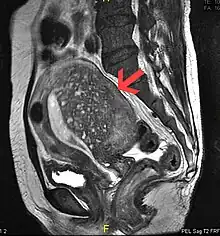

Magnetic resonance imaging

Magnetic resonance imaging (MRI) provides slightly better diagnostic capability compared to TVUS, due to the increased ability of MRI to differentiate objectively between different types of soft tissue.[22] This is possible with MRI's higher spatial and contrast resolution. Overall, it is estimated that MRI has a sensitivity of 74% and specificity of 91% for the detection of adenomyosis.[10] Diagnosis through MRI focuses predominately upon investigating the junctional zone. The uterus will have a thickened junctional zone with darker/diminished signal on both T1 and T2 weighted sequences.[22]

Three objective measures of the junctional zone can be used to diagnose adenomyosis.[22]

- A thickness of the junctional zone greater than 8–12 mm. Less than 8 mm is normal.

- A junctional zone width being greater than 40% of the width of the myometrium.

- Variability in the width of the junctional zone being greater than 5 mm.

Interspersed within the thickened, darker signal of the junctional zone, one will often see foci of hyperintensity (bright spots) on the T2 weighted scans representing small cystically dilatated glands or more acute sites of microhemorrhage.[22]

MRI is limited by other factors, but not by calcified uterine fibroids (as is ultrasound). In particular, MRI is better able to differentiate adenomyosis from multiple small uterine fibroids.